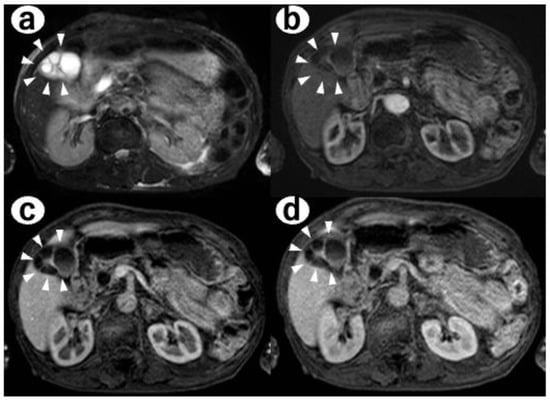

- Contrast-enhanced MRI: there was a 4-mm gallbladder body polyp and no abnormal signals in the thickened wall at the fundus of the gallbladder (Figure 3);